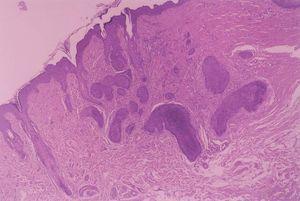

Se realizó extirpación quirúrgica de ambas lesiones (figs. 2 y 3).

Fig. 2.—Islotes de células basaloides con disposición en empalizada y reacción estromal abundante. (Hematoxilina-eosina, ×40.)

El estudio anatomopatológico puso de manifiesto la presencia de nidos de células epiteliales basaloides que en la periferia adoptaban una disposición en empalizada. Estaban situados fundamentalmente en dermis media y envueltos por una reacción estromal de condensación observándose en algunos de los islotes diferenciación ductal. Las lesiones del padre también correspondieron a tricoepiteliomas, si bien en la espalda se le extirpó un carcinoma basocelular.

Histológicamente, los tricoepiteliomas se clasifican según el grado de diferenciación del germen folicular, aunque genéricamente presentan islotes de células basaloides que, en algunas áreas, muestran una empalizada periférica, rodeadas de un estroma fibrocítico, que suelen mostrar diferenciación folicular hacia bulbo y papilas foliculares, respectivamente8 . El componente estromal es de gran importancia para establecer el diagnóstico diferencial con el carcinoma basocelular, ya que el tricoepitelioma presenta un estroma con abundante celularidad y cuerpos mesenquimatosos papilares, pero no inducción mucinosa, desmoplasia ni telangiectasias arboriformes. Es bastante frecuente la presencia de pequeños quistes de queratina recubiertos por epitelio escamoso estratificado que, si se rompen, provocan un pequeño granuloma a cuerpo extraño en el estroma. Las agregaciones de fibroblastos son características del tricoepitelioma9 . Las tinciones de inmunohistoquímica en los tricoepiteliomas muestran una fuerte afinidad para las citoqueratinas CK 5/6 y CK 8, y débil para CK 17 en las células que rodean a los quistes córneos10 . El protooncogén bcl2 , que codifica la proteína bcl2, que inhibe la apoptosis, es un marcador útil para el diagnóstico en casos de difícil diferenciación histológica11 .